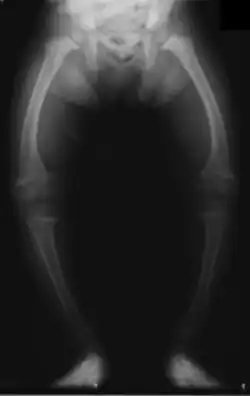

| X-ray of a two-year-old with rickets, demonstrating a marked bowing of the femurs and decreased bone density | |

An X-ray or radiograph of an advanced patient with rickets tends to present in a classic way: the bowed legs (outward curve of long bones of the legs) and a deformed chest. Changes in the skull also occur, causing a distinctive "square-headed" appearance known as "caput quadratum".[20] These deformities persist into adult life if not treated. Long-term consequences include permanent curvatures or disfiguration of the long bones, and a curved back.[21]

- Radiography typically shows widening of the zones of provisional calcification of the metaphyses secondary to unmineralized osteoid. Cupping, fraying, and splaying of metaphyses typically appear with growth and continued weight bearing.[50] These changes are seen predominantly at sites of rapid growth, including the proximal humerus, distal radius, distal femur, and both the proximal and the distal tibia. Therefore, a skeletal survey for rickets can be accomplished with anteroposterior radiographs of the knees, wrists, and ankles.[50]